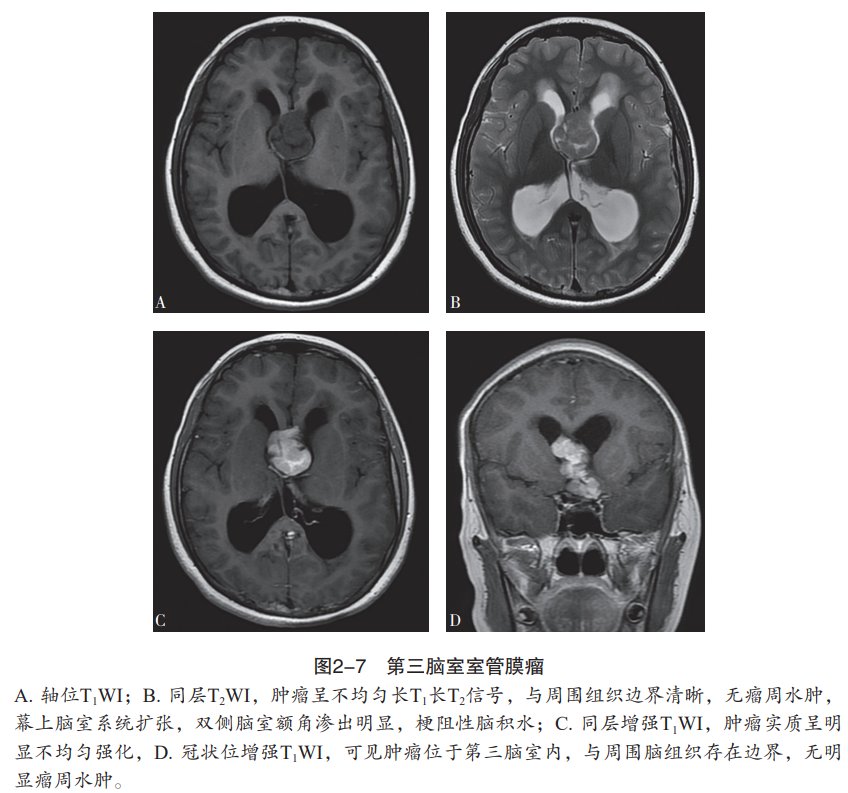

室管膜肿瘤的mri特点有哪些人卫书摘

图片尺寸848x793